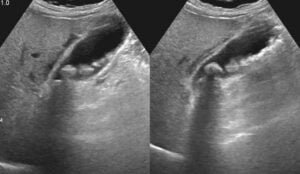

- Ultrasound: This imaging test is most commonly used to identify the presence of gallstones.